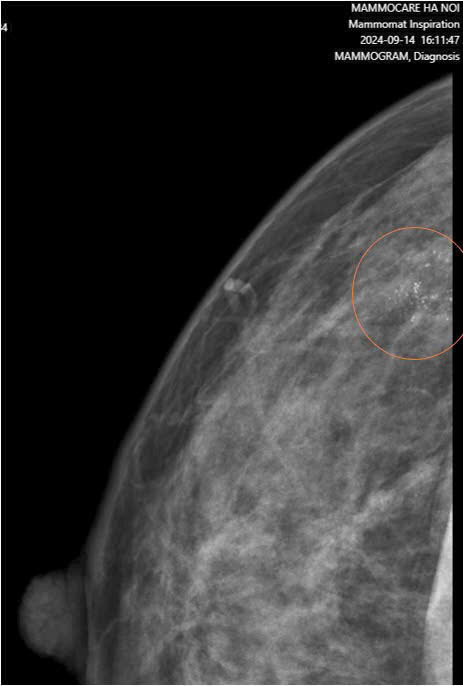

Kết quả chụp nhũ ảnh cho thấy hình ảnh vôi hóa đa hình và vô định hình, tập trung thành nhóm trong một vùng ~11x12mm ở vú phải. Kết hợp với siêu âm, bác sĩ phát hiện một khối giảm âm khá lớn (~7.8x42mm) – dấu hiệu cho thấy một tổn thương đáng ngờ.